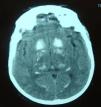

Symptomatic treatment for HF was started with diuretics, angiotensin-converting enzyme (ACE) inhibitors and nitrates, but there was little symptomatic relief and the hypocalcemia was investigated further. Hypocalciuria and hyperphosphatemia were also detected due to reduced parathyroid hormone levels (Table 3). Investigation of the etiology of hypoparathyroidism ruled out cancer, infiltration, and polyglandular and autoimmune syndromes, and a diagnosis of idiopathic hypoparathyroidism was made. Renal ultrasound showed no alterations and a cranial CT scan (Figure 4) detected extensive supratentorial calcification, more evident in the basal ganglia, suggesting typical chronic hypoparathyroidism.

In chronic forms of hypocalcemia, manifestations include cataracts, dental dysmorphisms and extrapyramidal symptoms due to calcification of basal ganglia.9,10